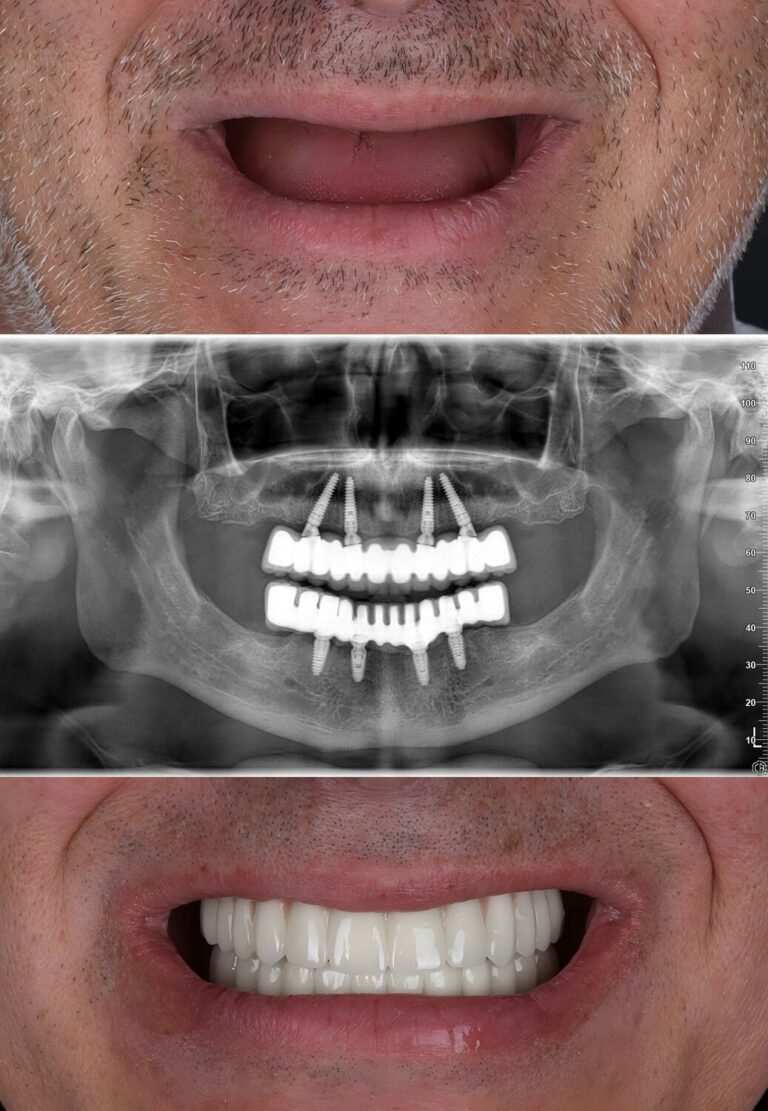

All-on-4 metoda koristi samo četiri implantata za potporu celog zubnog luka, što je čini znatno manje invazivnom od klasičnih metoda koje zahtevaju osam ili više implantata. Implantati se ugrađuju tako da se dva postavljaju vertikalno u prednjem delu vilice, dok se druga dva postavljaju (pod uglom od 30 do 45 stepeni) u zadnjem delu. Na taj način se maksimalno koristi postojeća kost bez potrebe za nadogradnjom.

• – Dva implantata se postavljaju uspravno u prednjem delu vilice

• – Dva implantata pod uglom u zadnjem delu za veću stabilnost

• – Privremeni zubni most se dobija odmah nakon ugradnje implantata

• – Obezbeđuje pun osmeh već istog dana